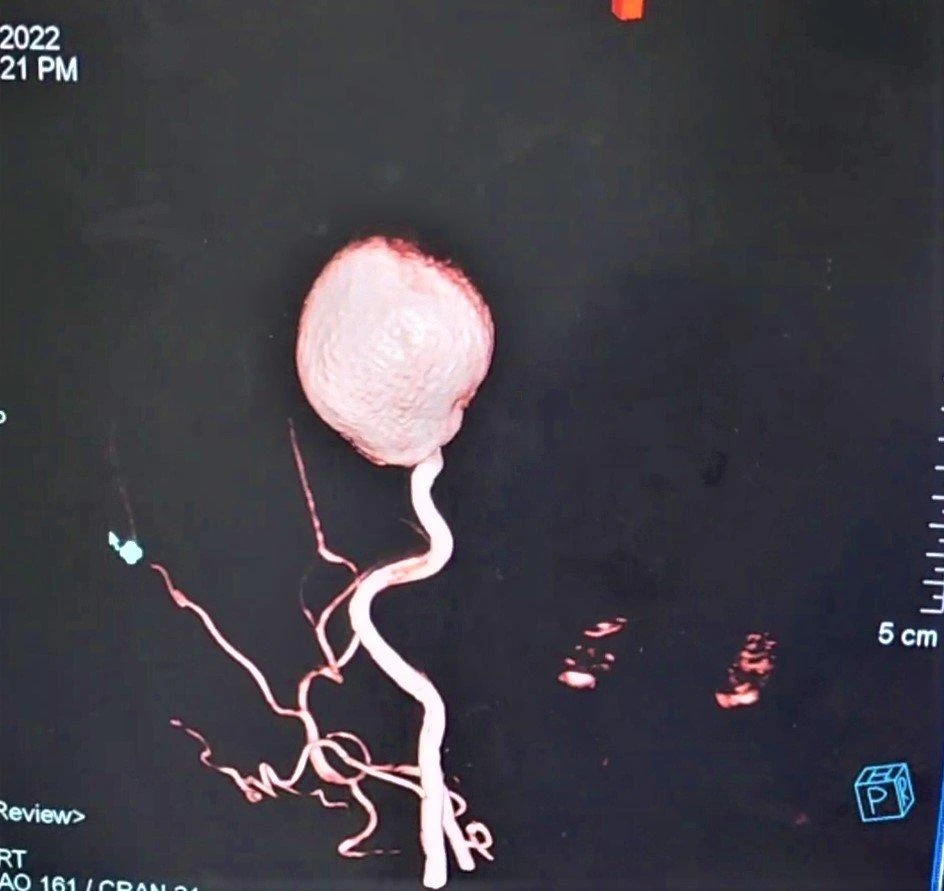

Hình ảnh động mạch cảnh khổng lồ. |

Khoa ngoại thần kinh đã tiếp nhận, thăm khám và hội chẩn chụp DSA mạch máu não phát hiện túi phình khổng lồ động mạch cảnh trong, với kích thước # 40mm. Sau đó bệnh nhân bị hôn mê do túi phình quá lớn chèn ép làm dãn não thất...